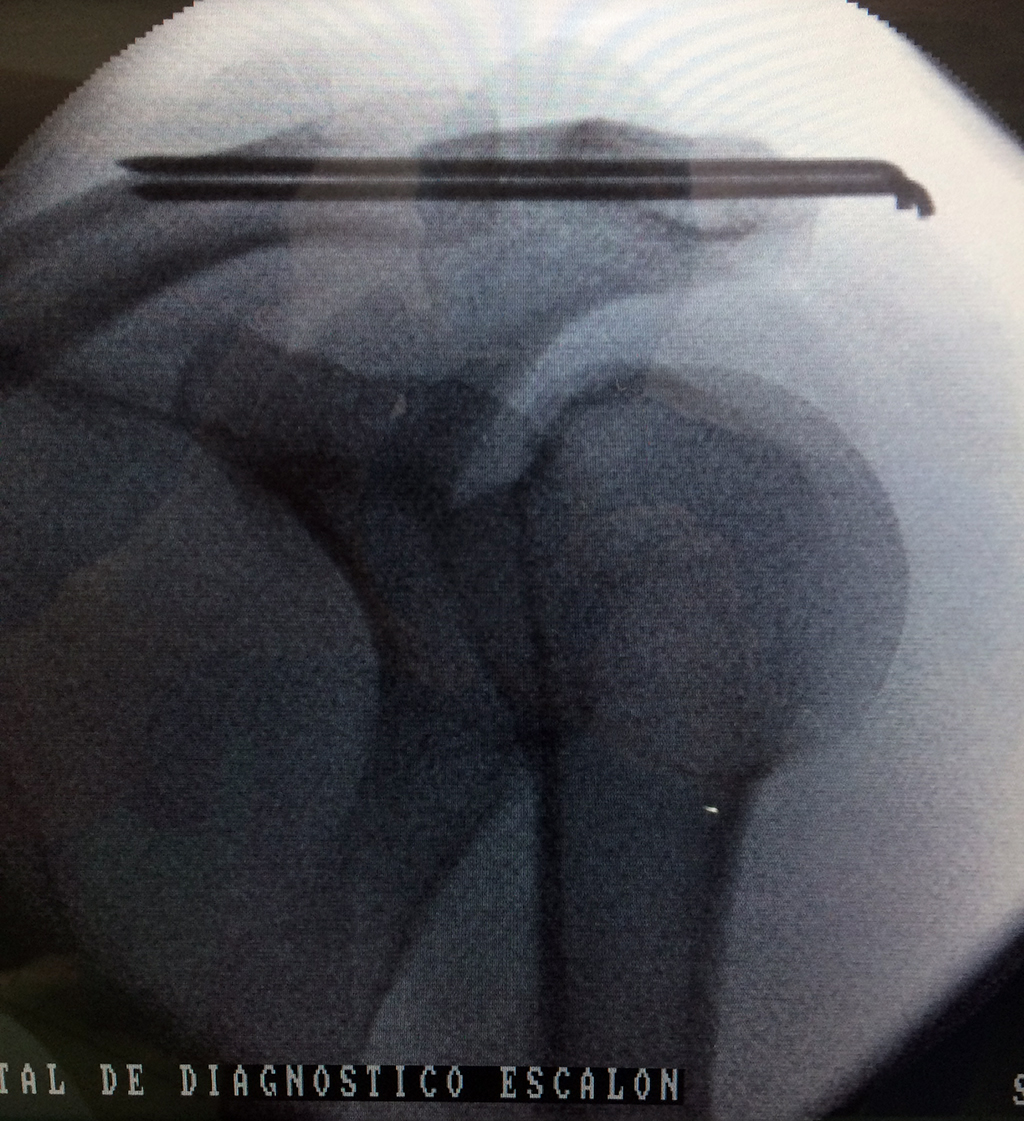

Cirugías de Codo - Clavícula

La clavícula es un hueso largo, con forma de "S" itálica, situado en la parte anterosuperior del tórax. Junto con la escápula forman la cintura escapular. Se puede palpar por toda su longitud y se extiende del esternón al acromion de la escápula, siguiendo una dirección oblicua lateral y posterior.